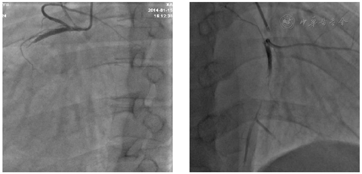

生活干预:戒烟戒酒、低盐低脂饮食、适当运动。药物治疗:阿司匹林肠溶片100 mg qd;氢氯噻嗪片25 mg qd;阿托伐他汀钙片20 mg qN;螺内酯片2 0mg,qd;单硝酸异山梨酯缓释胶囊50 mg,qd;比索洛尔片5 mg,qd;曲美他嗪片20 mg,tid;低分子肝素钙注射液0.4 ml,q 12 h。手术治疗:体外循环下行冠状动脉旁路移植术、人工三尖瓣置换术、上腔静脉-右肺动脉连接术。手术顺利,术中见心脏扩大,右房右室巨大,右室表面见大量散在花斑样梗死灶;三尖瓣瓣环扩大,直径6 cm,瓣口重度关闭不全;右冠状动脉直径1.5 mm

本例患者通过冠脉造影等明确了右室心肌梗死是巨大右心的病因,并通过冠状动脉旁路移植术+上腔静脉-右肺动脉连接术给予患者个体化的手术治疗,其显著的手术效果可能源于以下几点:(1)冠状动脉旁路移植术显著改善了右室心肌的血供,促进心肌的炎症消退、心肌细胞的存活、心肌组织的重塑,改善了心肌的收缩力和顺应性,从而提高了右心的射血分数、促进血液排出;(2)上腔静脉-右肺动脉连接术减少了右心的回心血量,降低了右心的前负荷,有助于患者心脏恢复正常大小,血流动力学更加稳定。(3)患者依从性好,坚持合理的生活干预和药物治疗。